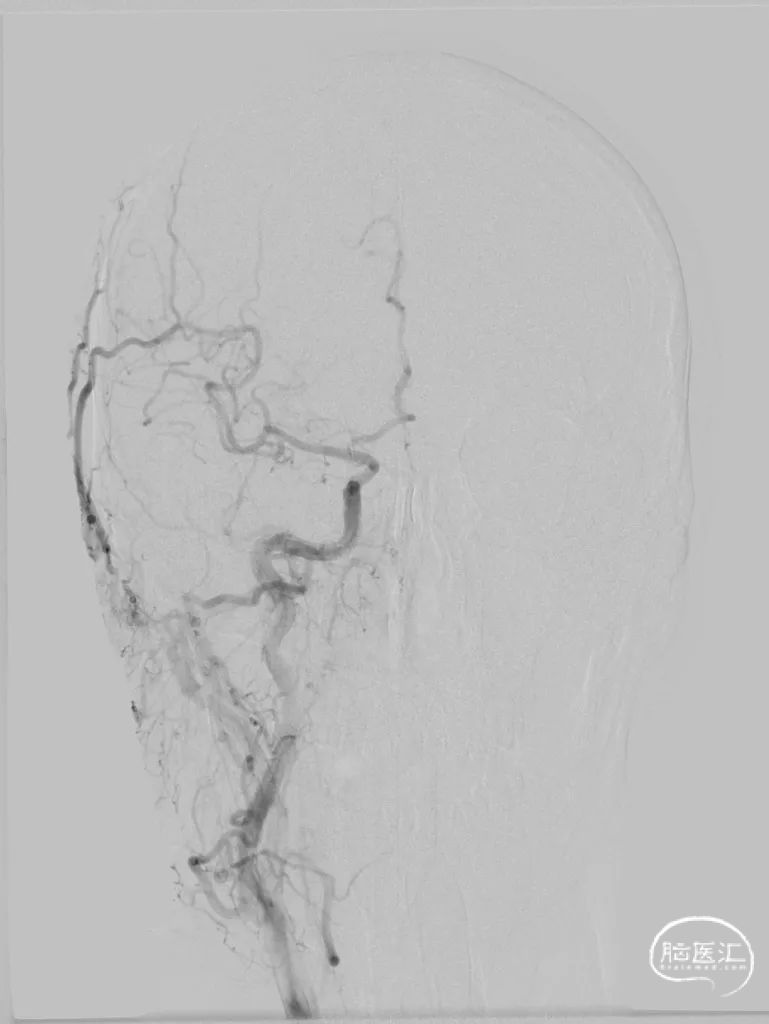

300cm微导丝携Gateway球囊到位,行球囊扩张及预扩张后造影。

小结和体会

1、本例患者反复出现神经功能障碍,血管评估提示双侧椎动脉V4段均为重度狭窄,左侧狭窄位置位于发出小脑后下动脉下方,紧邻小脑后下动脉,同时左侧小脑后下动脉起始段存在有重度狭窄,相对粗大。

2、右侧椎动脉V4段血管狭窄附近未见有明确血管分支,因此手术选择了行右侧椎动脉V4段球囊扩张及支架置入术,因双侧椎动脉V4段狭窄以远椎动脉及基底动脉汇合处血管良好,因此右侧椎动脉V4段狭窄处支架置入术后病人右侧椎动脉及远端基底动脉血流明显改善外,同时也可见到左侧椎动脉V4段逆向显影至左侧小脑后下动脉。同时避免了左侧椎动脉支架置入术中对左侧小脑后下动脉的影响导致小脑后下动脉缺血事件发生的可能。